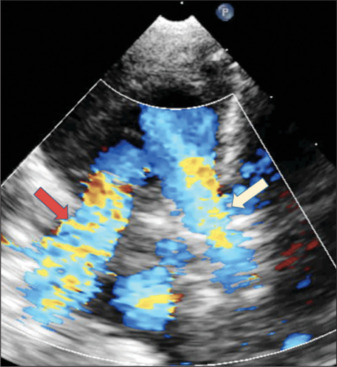

We describe a 7-day-old newborn who presented with arterial desaturation and respiratory distress. The evaluation showed a duct with a continuous right-to-left shunt and an anomalous origin of the right pulmonary artery from the aorta. We discuss the hemodynamics leading to continuous right-to-left ductal flow and the subsequent intraoperative evaluation that resulted in a successful single-stage surgical repair of this interesting case.